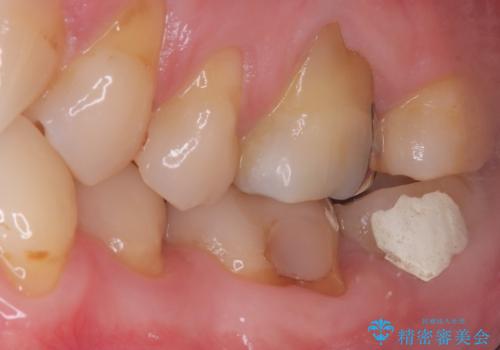

- 患者様は、他院で根管治療を受けたものの、違和感が続くため「しっかりとした治療を受けたい」とのご希望で来院されました。診査の結果、根管内の感染が完全に除去されておらず、根の先に炎症が残っている状態でした。そこで、精密根管治療を行い、感染源を徹底的に除去する計画を立てました。マイクロスコープを使用し、4回の治療で根の内部を清潔にし、最終的にしっかりと密封することで、長期的な安定を目指しました。

治療は、まず根管内の古い充填材を取り除き、感染部分を徹底的に洗浄・消毒することから始めました。ラバーダム防湿を使用し、治療中の細菌感染を防ぎながら、マイクロスコープを用いて根管の細部まで確認しながら処置を進めました。4回の治療で感染の除去と根管の封鎖を行い、最終的に土台を立てて被せ物の準備を整えました。患者様からは「違和感がなくなり、噛んでも痛くない」と喜びの声をいただきました。